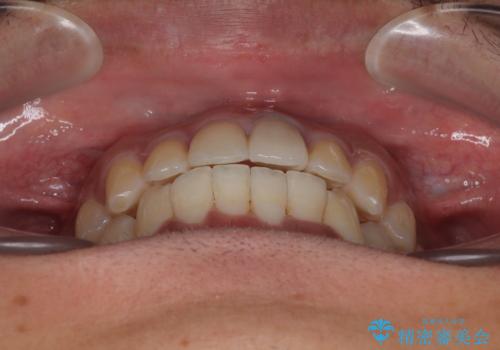

気になる前歯のデコボコと八重歯 ワイヤー矯正ですっきりと

矯正治療後には気になっていた前歯をセラミッククラウンにし、自然な口元に仕上げることができました。